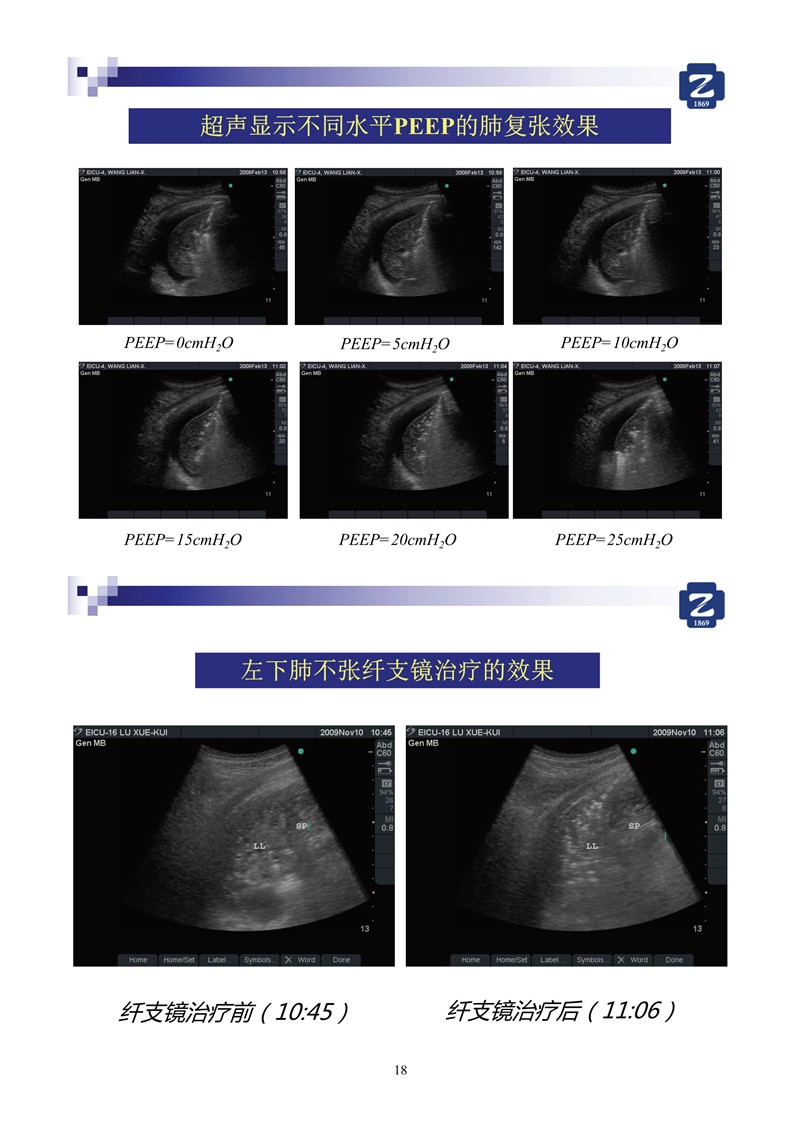

第二版新型冠狀病毒肺炎超聲診斷實用手冊_64.jpg